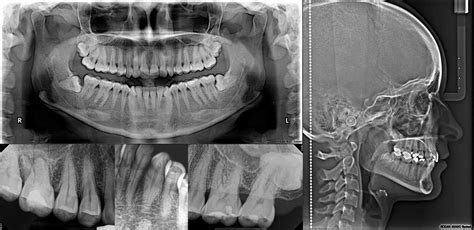

Ortopantomografía (Radiografía Panorámica)

La radiografía panorámica dental, también conocida como ortopantomografía, es una herramienta vital en el diagnóstico dental moderno. La radiografía panorámica dental o la ortopantomografía, permite tener en una sola película, una imagen general de la boca a nivel panorámico que muestra los maxilares, la mandíbula y los dientes.

El coste de una radiografía panorámica dental puede variar en función de la clínica y el equipo utilizado, pero suele oscilar entre 30€ y 80€.

Telerradiografía de Cráneo

La Telerradiografia de cráneo, es una radiografía de la cabeza del paciente. Consiste en una radiografía de la cabeza del paciente a una distancia mayor de lo habitual. En este estudio se pueden detectar anomalías con relación entre el maxilar y la mandíbula y la relación de estos con el resto de huesos del cráneo.

Tiene la desventaja en relación con el Tac 3d, que se una radiografía de dos dimensiones, todo lo vemos aplanado. Vemos a lo alto y a lo ancho pero no el grosor.